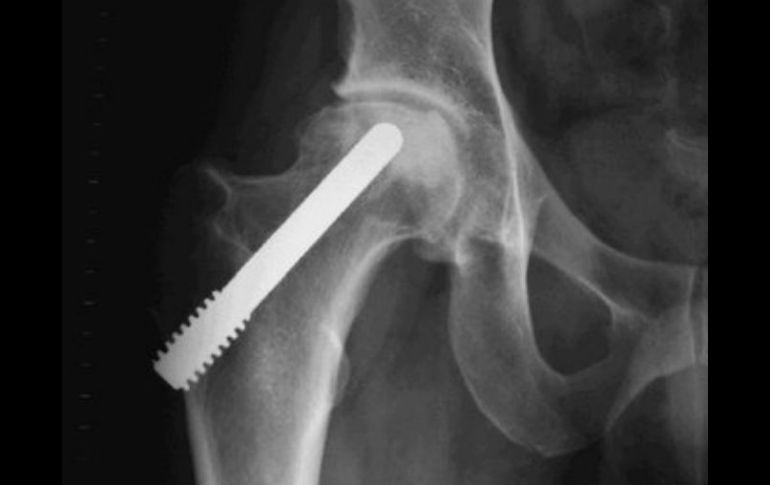

Tecnología | Presentan línea de prótesis económicas y tratamiento para cáncer óseo a partir de calor Mexicanos crean nuevas prótesis óseas y técnicas contra tumores Médicos presentan línea de prótesis más económicas y tratamiento a partir de calor para combatir el cáncer de hueso Por: NTX 20 de enero de 2014 - 20:40 hs Señalan que algunas piezas importadas no siempre servían porque eran muy grandes para la talla de pacientes mexicanos. ARCHIVO / CIUDAD DE MÉXICO (20/ENE/2014).- Médicos mexicanos desarrollaron una novedosa técnica para atender los tumores óseos a partir de calor y diseñaron prótesis de manufactura nacional que disminuyen los altos costos y otros problemas técnicos que provocaban las importadas. Los especialistas del Instituto Nacional de Rehabilitación, Genaro Rico, Javier Linares y Roberto González, mostraron una línea mexicana de prótesis para reconstrucción fémur, rodilla, húmero, cadera y en general huesos de brazos y piernas con cáncer óseo. En conferencia de prensa, Genaro Rico, jefe de Servicio de Tumores Óseos de dicho Instituto, detalló que la investigación del equipo multidisciplinario de oncólogos y especialistas fue desarrollada en los últimos 23 años en dicho centro. Refirió que en 1990 se iniciaron las cirugías para colocar prótesis del país, pues las importadas utilizan un cemento que ocasiona alteraciones de la mecánica del hueso, además de que no siempre servían porque eran muy grandes para la talla de pacientes mexicanos. Otros de los beneficios de estas prótesis de manufactura mexicana son que tienen un costo mucho menor, pues las adquiridas del extranjero, por ejemplo la de rodilla, puede tener un valor de hasta 400 mil pesos, expuso. Comentó que en esta investigación se concluyó que no sólo se tendría que trabajar en la opción de colocar prótesis a los pacientes con tumores óseos, por lo que con el Departamento de Biomédica de dicho Instituto se diseñó un "generador de vapor" que permite "salvar hueso". A nivel mundial, precisó, el calor es un cuarto pilar para el tratamiento del cáncer óseo, pues en primer lugar está la cirugía, seguida de la quimioterapia, radioterapia, por lo que con ese aparato se logra "ahorrar" hueso en candidatos a amputaciones. Detalló que con ese sistema, los pacientes con cáncer óseo o de tejido en extremidades logran salvar hasta 80 por ciento de sus huesos a partir de una técnica llamada Hipertemia Hídrica Controlada (HHC), que consiste en introducir la parte del cuerpo a agua con temperatura de más de 40 grados centígrados. En ese tenor, el doctor Roberto González explicó que el llamado generador de vapor o HHC ha sido utilizado en el tratamiento de al menos un centenar de pacientes con resultados exitosos, aunque aún continúa en fase de investigación. El especialista detalló que las células tumorales se mueren a más de 40 grados centígrados y que pese a que en el tratamiento suele haber quemaduras en piel, los beneficios son mayores porque se logra salvar hueso y con ello la posibilidad de que las personas no requieran prótesis o éstas sean menores. En tanto, el doctor Genaro Linares, dijo que las prótesis mexicanas están patentadas y son fabricadas en Puebla, y a la fecha han sido colocadas casi 300, muchas de ellas a pacientes de escasos recursos, que son apoyados por fundaciones e instituciones. Temas Estudios científicos Cáncer Ciencia médica Enfermedades Lee También Julieta Fierro será homenajeada en la FIL INAPAM: ¿Cómo solicitar un turno para consulta médica gratuita? Octubre Rosa: ¿Cuánto cuesta una mastografía en Jalisco según Profeco? Nobel de Química premia el desarrollo de estructuras metal-orgánicas Recibe las últimas noticias en tu e-mail Todo lo que necesitas saber para comenzar tu día Registrarse implica aceptar los Términos y Condiciones